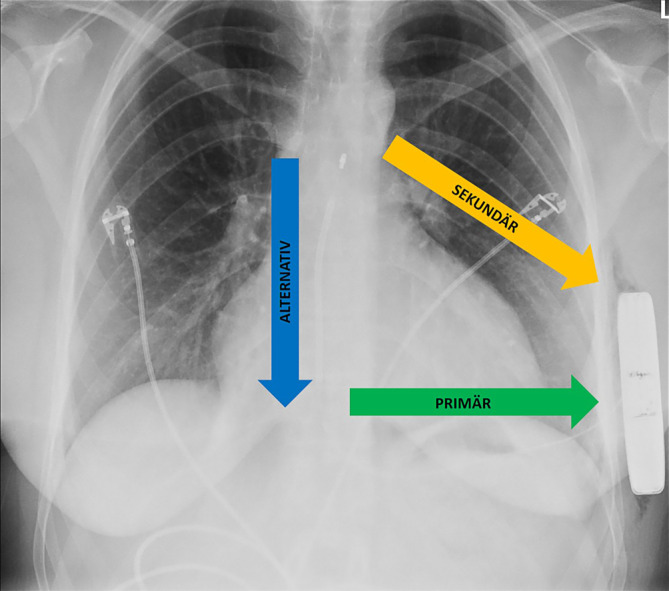

As an alternative to transvenous ICD systems, two non-transvenous ICD systems have been established in recent years: The subcutaneous ICD (S-ICD), which has been established for several years, has a presternal electrode that is implanted subcutaneously and offers a shock function and, to a limited extent, post-shock pacing. In addition, the extravascular ICD (EV-ICD) has been available in Europe since 2023 which does not require transvenous electrodes and offers the option of providing patients with antibradycardic and antitachycardic stimulation in combination with a conventional ICD function. The lead of this device is implanted substernally. Initial implantation results are promising in terms of safety and effectiveness. Both systems avoid possible complications of transvenous electrodes. This article provides practical guidance for the implantation technique and possible complications.

作为经静脉 ICD 系统的替代方案,近年来出现了两种非经静脉 ICD 系统:皮下 ICD(S-ICD)已问世数年,其胸骨前电极植入皮下,具有电击功能,并在一定程度上提供电击后起搏。此外,血管外 ICD(EV-ICD)已于 2023 年在欧洲上市,它不需要经静脉电极,可为患者提供抗心动过缓和抗心动过速刺激以及传统的 ICD 功能。该设备的导联是在体下植入的。就安全性和有效性而言,初步植入结果令人满意。这两种系统都避免了经静脉电极可能出现的并发症。本文就植入技术和可能出现的并发症提供实用指导。